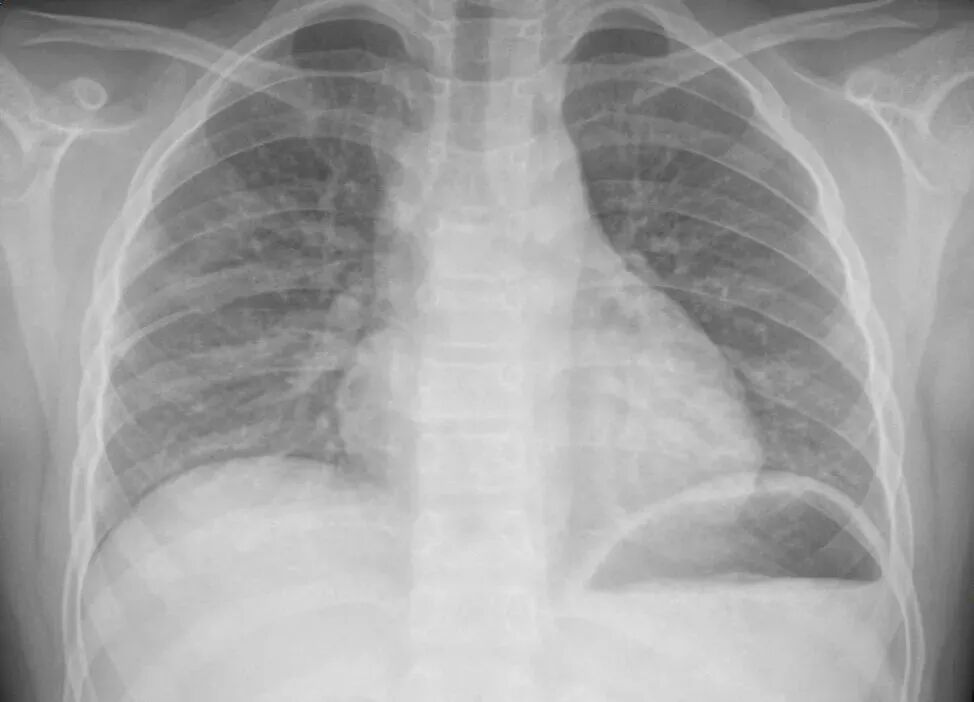

结果,不久两个孩子都出现了阵发性刺激性干咳,还出现了头痛、呕吐,家人赶紧送到医院就诊,胸片检查显示,有肺炎征象,医生及时给予治疗。

胸片提示两肺散在可疑斑片影,胸部CT提示两肺炎症性改变,医生拟“过敏性肺炎”收住入院。由于肺部有渗出,没办法进行正常气体交换,氧气进不到血里,朵朵还一度因为缺氧被下了病危通知。

医生表示,“白肺”一般是指重症肺炎在X线或CT检查下的表现,患者肺部呈现一大片的白色状态,往往会出现呼吸困难、呼吸衰竭,严重者还会出现其他脏器功能障碍。

感染、弥漫性肺泡出血综合征等是“白肺”最常见的病因,除此之外,吸入有害物质如粉尘、喷雾等也可能会导致肺部出现大范围白色样病变,也就是说如果长期不正确使用防晒喷雾,有可能导致“白肺”。